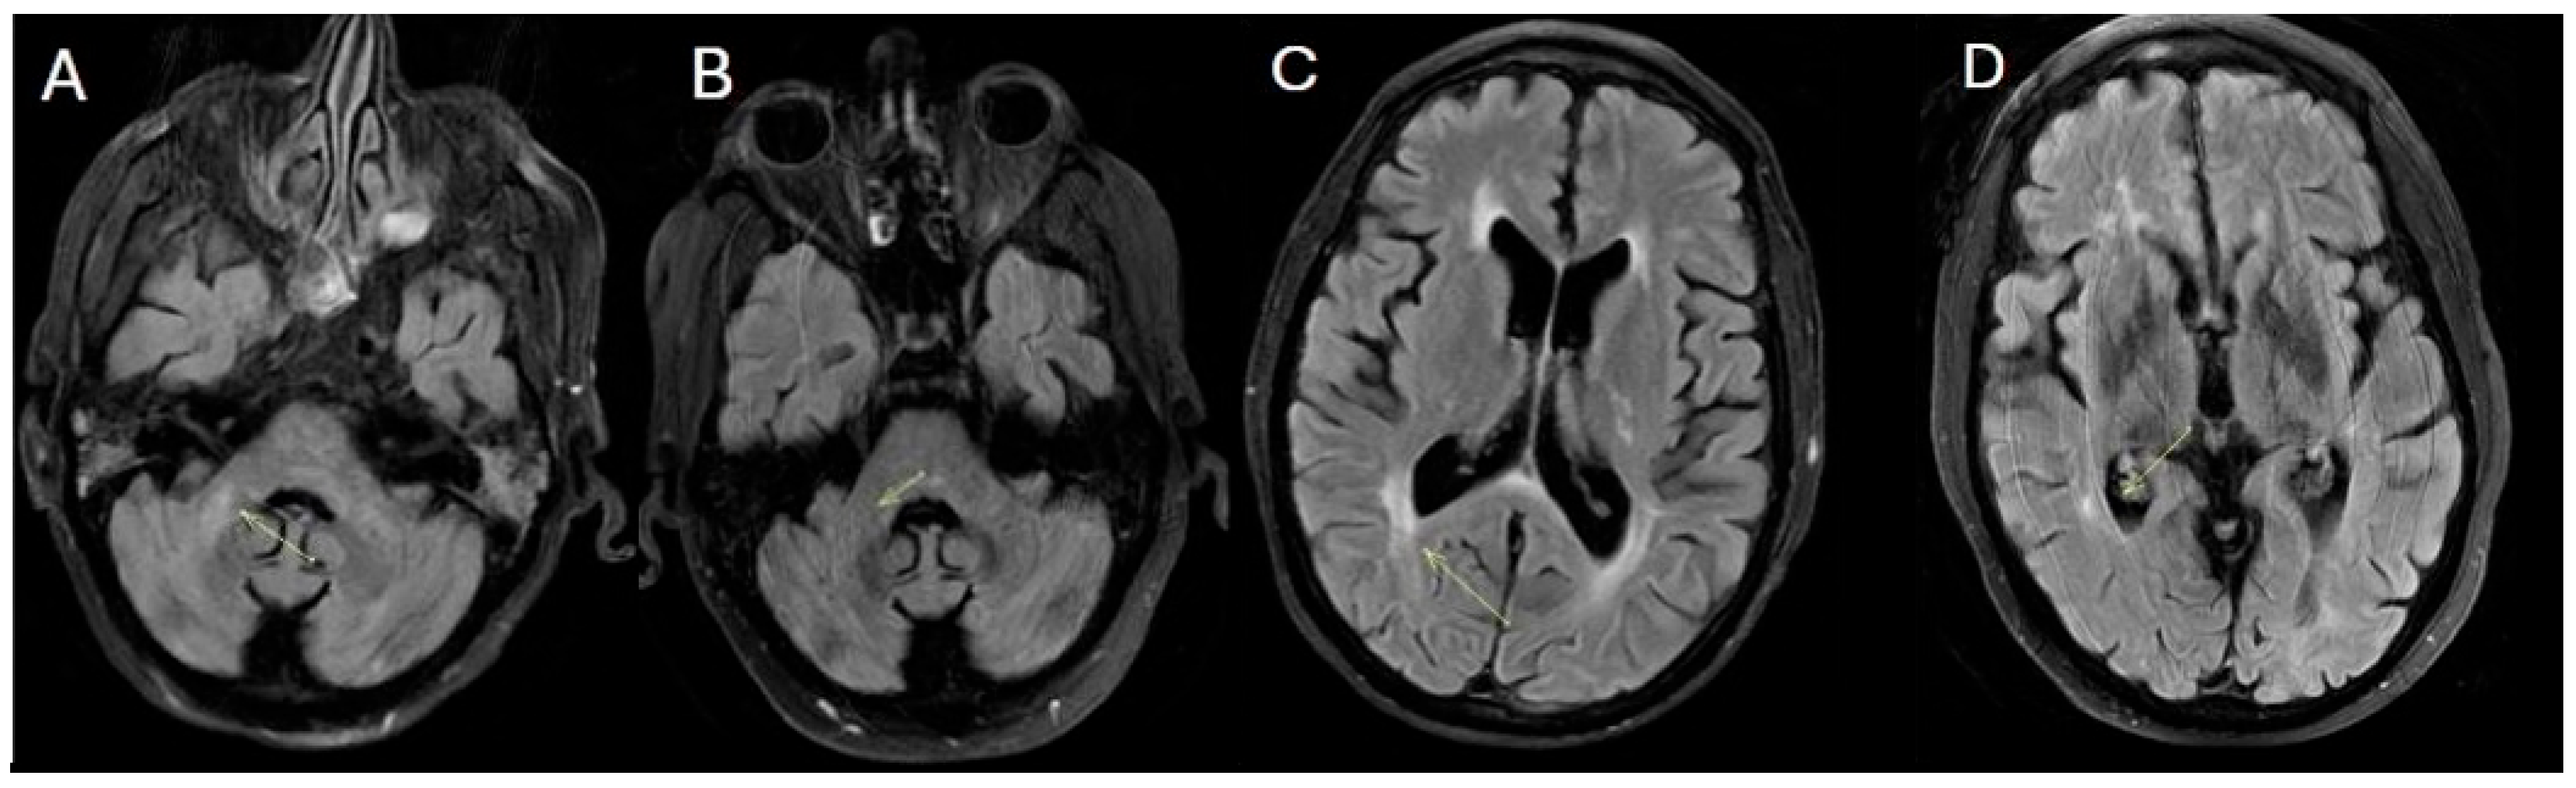

During the final hospitalization in March, follow-up MRI revealed early radiological signs of disease reactivation, without clear laboratory evidence of relapse (Figure 4).

Figure 4. Fluid-attenuated inversion recovery (FLAIR) (AD) (March 2025). The images show the appearance of a new hyperintense signal alteration on FLAIR in the right middle cerebellar peduncle and an increase in the hyperintense signal alteration on FLAIR in the right paratrigonal region.